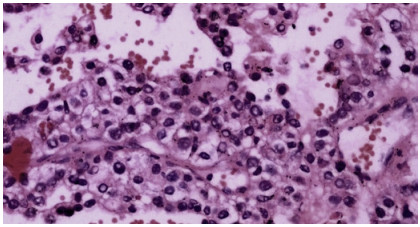

Abstract: Hepatic EHE (epithelioid hemangioendothelioma) is an uncommon entity of vascular origin and a low-grade malignant tumor. Primary hepatic EHE is rare. These tumors can be multifocal at presentation like in the soft tissues, bones, brain, liver, and small intestine. First described by Weiss and Enzinger in 1982 as a malignant vascular neoplasm with indolent behavior. We report the case of a 23-year-old male, known case of chronic liver disease, who presented with incisional hernia following exploratory laparotomy 8 months back, performed for intestinal obstruction. Contrast-enhanced computed tomography abdomen revealed an incisional hernia with a large defect along with multiple lesions in the liver (suspected metastases) and peritoneal deposits and a few discrete lung nodules. Some areas of interloop collections were also noted. Biopsies were taken from the liver which revealed benign cirrhotic lesion. Relevant to the findings, multiple biopsies were performed and fluid was sent for evaluation. The liver biopsy came out positive for borderline vascular malignancy (epithelioid hemangioendothelioma). This was confirmed with the immunohistochemistry report. Epithelioid hemangioendothelioma occurs mostly in soft tissues of extremity and lungs. The involvement of the liver may be seen as metastasis or rarely as a primary tumor. The incidence of primary malignant hepatic hemangioendothelioma is about 0.1/100,000; the mean age at the time of diagnosis is 41.7 years, and male:female ratio is 2:3. Liver transplantation, hepatectomy, chemoembolization, radiotherapy, and chemotherapeutic agents are reported treatment regimens. Malignant EHE of liver presents as multiple hepatic nodules. Being locally aggressive, it can invade the peritoneum, gut, and lungs. Orthoptic liver transplantation appears to be the only remedy because of the multifocal nature of the disease. Partial hepatectomy is possible for localized tumors.